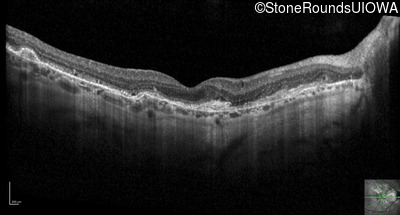

Optical Coherence Tomography - Right - 20/20 -1

Exemplar / OCT Stack

OCT Stack